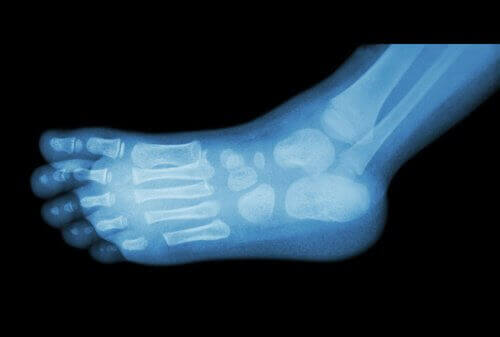

Läkare använder röntgen för att diagnostisera hälsporre.